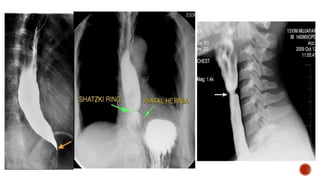

Barium swallow is a

dedicated test of

the pharynx, oesophagus

and GE Junction.

Barium swallow isa dedicated test of the pharynx, oesophagus and GE Junction.

 Dysphagia andobstruction.  Pain during swallowing.  Assessment of mediastinal masses.  Assessment of left atrial enlargement.  Pre-op assessment of carcinoma bronchus and oesophagus.  Motility disorders of oesophagus, E.g.: Achalasia and diffuse oesophageal spasm, scleroderma.  Assessment of site of perforation.  Zenker's diverticulum and cricoid webs.

 Tracheo-oesophageal fistula. Perforation.  Leakage of barium from an unsuspected perforation-granuloma formation.  Aspiration.

Nil orally for6 h prior to the examination. The patient is advised not to smoke on the day of the examination, as it increases gastric motility. It should be ensured that there are no contraindications to the Preliminary film Technique or pharmacological agents used.